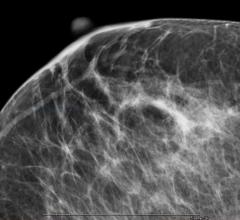

The U.S. Preventive Services Task Force (USPSTF) has released a draft of its newest recommendations for breast cancer screening. These are available for public comment through May 18.

The American College of Radiology (ACR) and Society of Breast Imaging (SBI) have issued a statement saying that adoption of draft United States Preventive Services Task Force (USPSTF) breast cancer screening recommendations would result in thousands of additional and unnecessary breast cancer deaths each year.